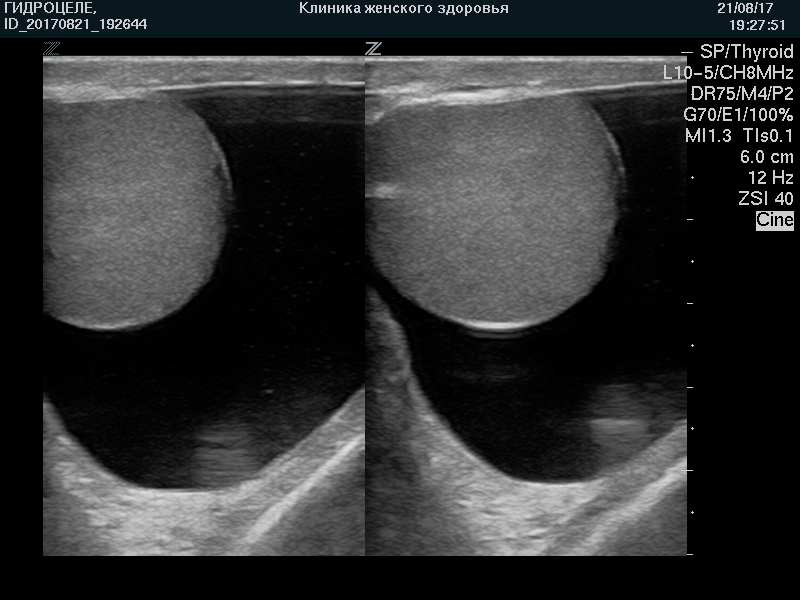

Ультразвуковая картина водянки яичка, гидроцеле, кисты придатка яичка, сперматоцеле, кисты семенного канатика, фуникулоцеле ХАРАКТЕРНА и сомнений не вызывает.

УЗИ мошонки позволяет безопасно (без «облучения») осуществлять динамический контроль на фоне лечения и/или наблюдения.

| Водянка яичка. Свободная жидкость контурирует яичко |

|

| Водянка яичка. Тот же случай. |